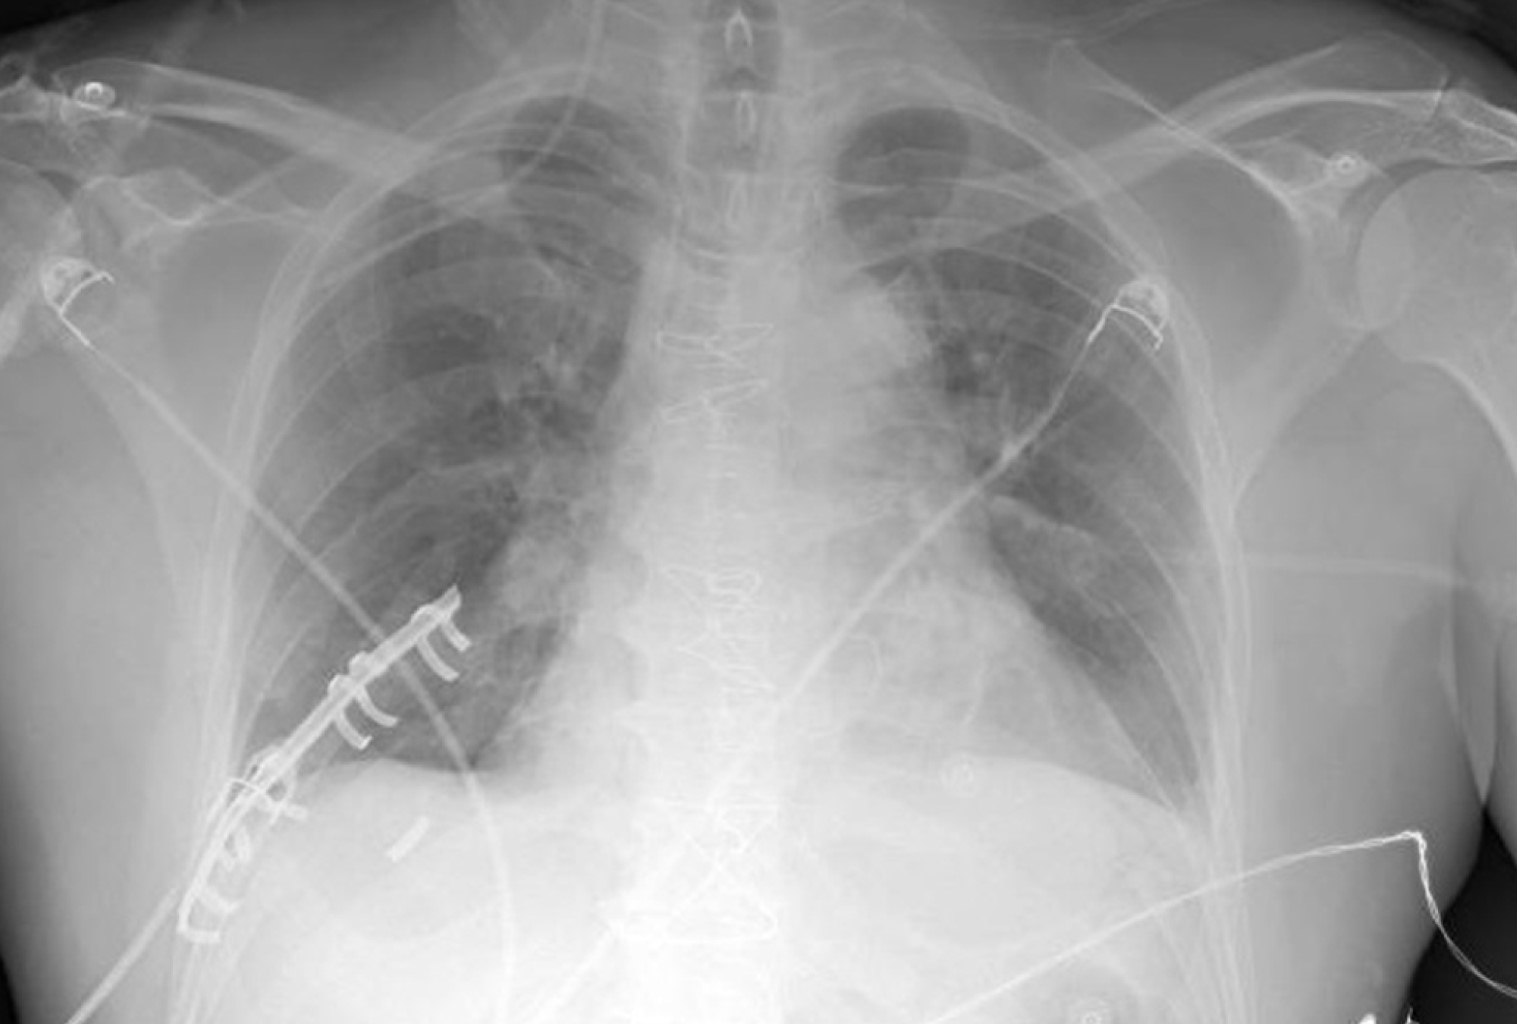

Malposition of central venous catheters is associated with important and underestimated risks. Although some factors have been related with malposition, its cause is generally not diagnosed, and it seems to have multifactorial origin. We present two cases of central venous catheter malposition due to unusual anatomical causes, diagnosed in the perioperative period. In the first case, superior vena cava agenesis was diagnosed during mitral replacement by sternotomy, which was logically associated with malposition of the inserted central line. The use of catheters and devices through jugular and subclavian veins in patients with this infrequent pathology is associated with important limitations and serious potential complications. In the second case, an undiagnosed goiter causes bilateral and simultaneous malpositioning of two inserted central venous catheters, in the context of an emergency situation, in both internal jugular veins.

Figure 1

Figure 2

Figure 3

Figure 4

Figure 5